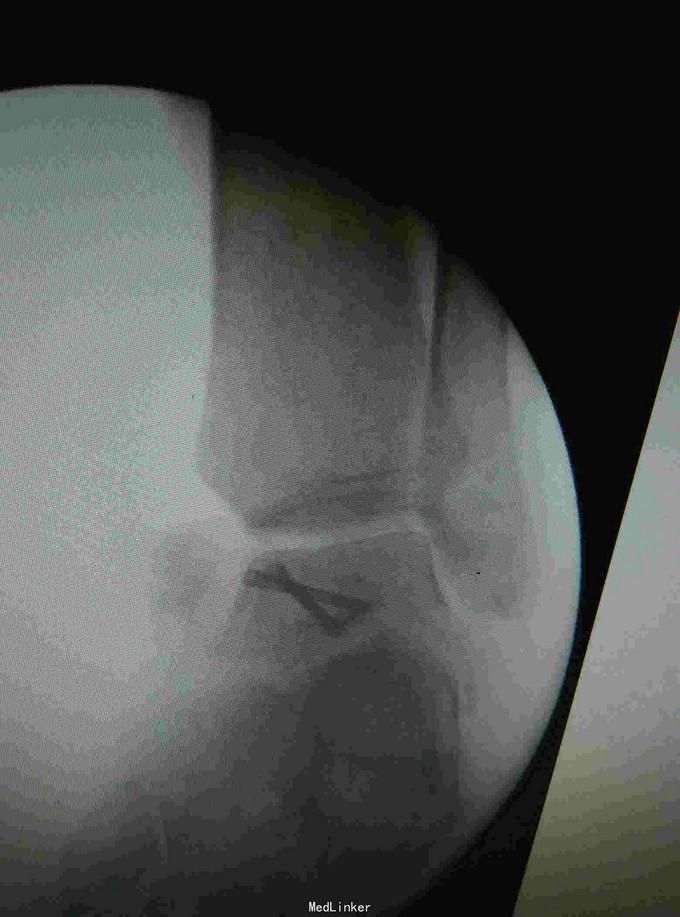

患者,男,45岁,车祸伤致右踝部肿痛,活动受限2小时入院

入院查体见局部肿胀,予完善影像学检查,

诊断是右距骨粉碎性骨折。给予行内踝截骨显露骨折端进行复位,采用Herbert钉进行固定。